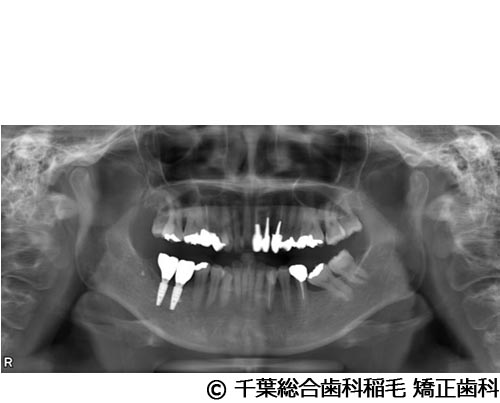

【症例1】下顎大臼歯3本インプラント埋入手術

- 治療前

- 治療後

- 治療名

- 下顎大臼歯3本インプラント埋入手術

- 費用

- 1,400,000円(税込)

- 期間

- 10ヵ月

治療内容

-

患者様の症状

左下第一大臼歯は他院で治療中でしたが、治療がなかなか進まず、他の部位にもお痛みが続いていたため、当院にご相談に来られました。

治療法

左下第一大臼歯は保存が厳しい状態だったため、抜歯となりました。

ご来院時から欠損状態だった右下第一、第二大臼歯も含め、欠損補綴についてお話させていただき、インプラントでの治療を選択されました。 -

治療結果

お痛みも和らぎ、現在も定期検診で拝見させていただいています。

※治療結果は患者様によって個人差があります。